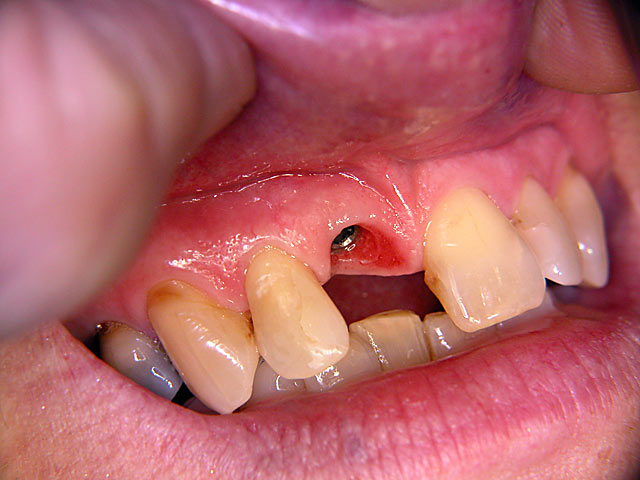

Sofort-Implantation: